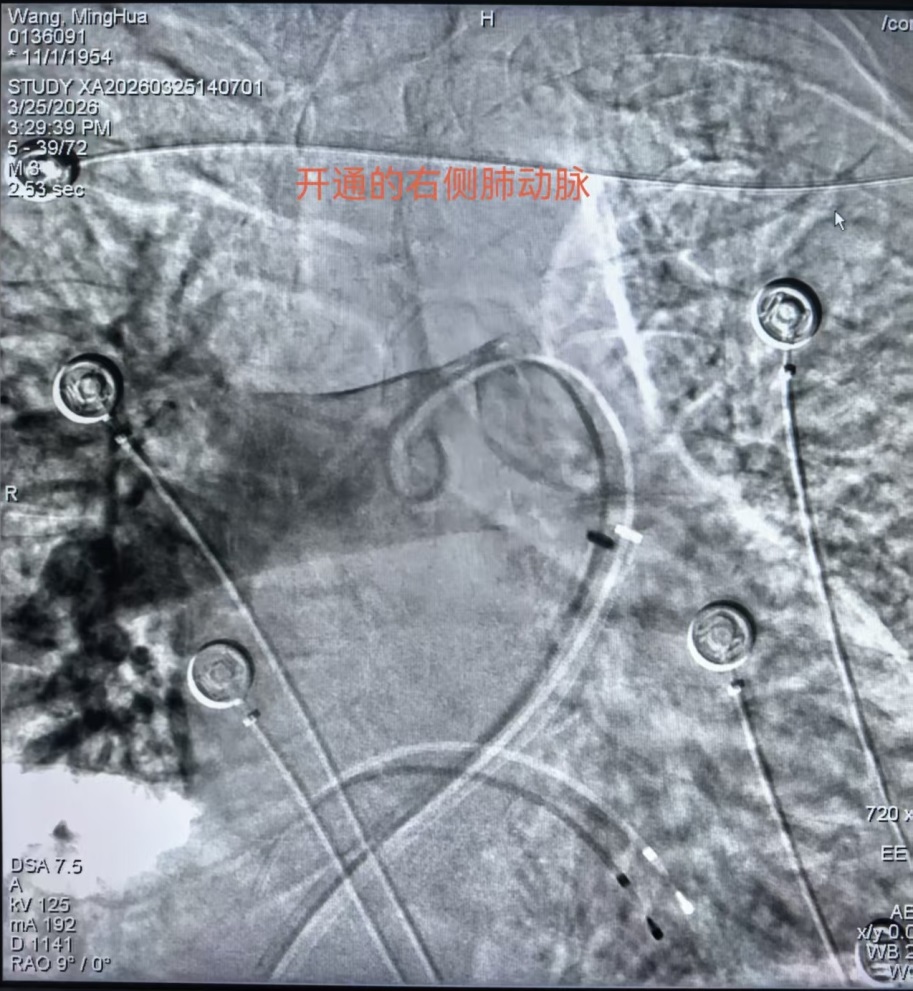

面对突发状况,护理人员沉着冷静,迅速配合医生完成左股静脉穿刺并置入临时起搏器,经测试起搏效果良好,患者心率成功恢复并维持在80次/分,为后续取栓操作创造了安全的身体条件。在血栓抽吸的关键环节,护理人员精准递送各类专用器械,密切配合医生开展双侧肺动脉血栓抽吸操作,成功抽出大量红、白色血栓。操作过程中,护理人员持续严密监测患者生命体征变化,根据手术需要及时追加肝素钠注射液进行抗凝处理、补充碘造影剂,全程保障手术安全、高效推进。

术后造影显示,患者双肺动脉充盈缺损情况明显改善,肺部血流灌注恢复良好。术中抽取的约400ml血液,经专业过滤去除血栓后,护理人员协助医生全部回输给患者,有效维持了患者的循环稳定。手术结束后,护理人员严格按照拔管后护理规范,对患者穿刺部位进行加压包扎,术后持续严密观察患者下肢血运情况,做好各项基础护理工作。